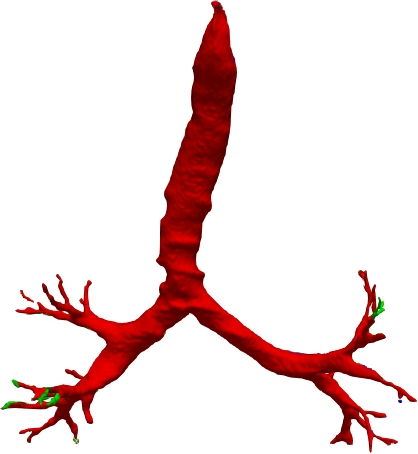

However, current state-of-the-art methods of lung organ segmentation still face several challenges and aspects for improvement. Firstly, the unlimited voxel values, multi-site imaging discrepancy and class imbalance in lung organ images can lead to false-negative and leakage issues in prior segmentation methods, which badly influences the critical early diagnosis of imperceptible lung diseases, e.g., lung fibrosis, nodule and hypertension, etc. Secondly, the presence of numerous slender branches, e.g., bronchioles and arterioles, which are easily lost during the recycled down/up-sampling procedure in Fig. 1, can result in discontinuity, detail loss, and coarse mask predictions. Thirdly, most CNN-based medical segmentation methods treat all points equally during the mask rendering stage, overlooking the vulnerability of border points in Fig. 1 (f) and the importance of explicit border modeling. Lastly, while Vision Transformer (ViT) has shown promise in computer vision tasks [1, 4], its quadratic operation complexity limits its application in 3D high-resolution CT images due to hardware constraints. Meanwhile, most specific datasets for medical image analysis are small and scarce due to laborious manual annotation and privacy protection, which badly restricts the potential of transformer-based top-tier methods.

2.2 Global-Local Cube-tree Fusion

To the best of our knowledge, most mask render-based two-stage semantic segmentation methods [6, 21] operate equally on all dense points of the coarse masks to improve the final performance, which is unnecessary to focus much on the already correctly predicted points. As shown in Fig. 1 and according to our statistical error analysis, most very vulnerable points occur on the object border due to the information loss caused by down-sample operation in the encoding process, especially for the innumerable bronchioles or arterioles in the tree-like structures. Thus, we only focus on the border vulnerable points and propose the novel global-local cube-tree fusion module. Specifically, (1) we “recycle” the down-sample and up-sample operations to produce masks and , and evaluate the absolute difference of them in Fig. 1 to get the border vulnerable points for the -th layer; (2) as shown in the top-right side of Fig. 2, we build the cube-tree of the -th point by extracting the local contextual features of {26, 27}-neighbors of the {, +1}-th layers respectively, which are defined as the cube without and with centroid. For the last layer, it is of note that we extract the 27-neighbors’ local contextual features in the adjacent layer -1; (3) we flatten features in the spatial dimension and project them as well as centroid feature into three vectors , which are separately related to the fine grain, coarse grain local context information and cube-tree centroid feature; (4) global airway or artery features from the distribution of the whole dataset is also very important, hence, we introduce the learnable global features to yield the projected global features , where is the embedding dimension; (5) we fuse the four features into as follows:

We qualitatively analyze our method on four challenging lung organ datasets. In Fig. 5, SFCN [19] suffers from severe false positives and some false negatives, especially for the big green areas of airway leakages. WNet [22] is mainly influenced by false negatives on the main trachea. For the Fibrosis dataset at the third row, it also encounters the false negative problem in the terminal bronchioles moderately. FANN [10] bears the slight discontinuity issue of false negative in the terminal bronchioles of BAS dataset, and the severe discontinuity and airway leakage problems on the more challenging Fibrosis benchmark. Instead, due to the above two novel modules, our method can solve the defects of false negative, discontinuity, and leakages faced by past advanced methods. Besides, the results on PARSE22 artery dataset in supplementary Fig. 6 also proves this.